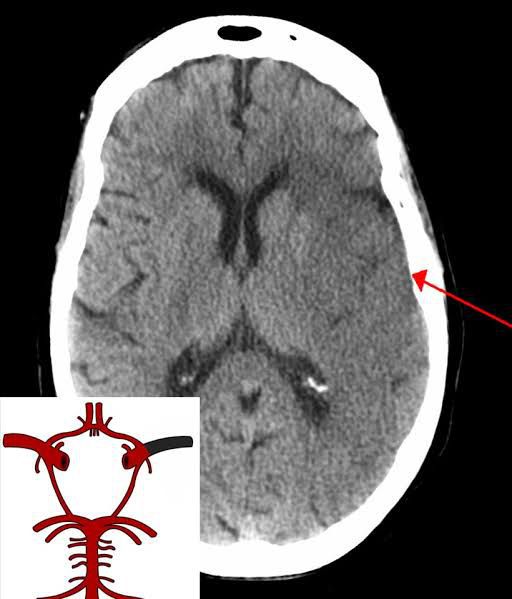

Bamford and colleagues used data from the Oxford Community Stroke Project to define four sub-categories of cerebral infarction on the basis of presenting symptoms and signs: lacunar infarcts (LACI); total anterior circulation infarcts (TACI); partial anterior circulation infarcts (PACI); and posterior circulation ...